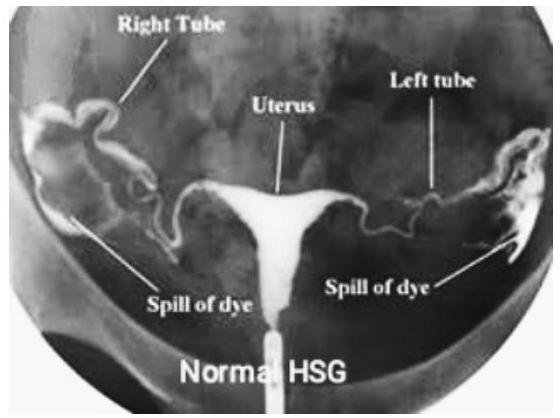

# LIIFERTILIDAD y ESTERILIDAD ## DEFINICIÓN INFERTILIDAD: FALLA de una pareja para CONCEBIR POSTERIOR A 12 MESES DE RELACIONES SEXUALES sin el uso de anticoncepción, en mujeres menores de 35 años de edad o posterior a 6 meses en mayores de 35 años. ESTERILIDAD: Es un término que ANTERIORMENTE se utilizaba para designar a los pacientes que lograban tener una prueba de embarazo positiva pero que tenían perdidas constantes del producto sin poderlo llevar a término. - Esterilidad Primaria: incapacidad de conseguir una gestación espontánea desde el inicio de las relaciones sexuales sin que, al menos durante un año, se hayan utilizado anticonceptivos. - Esterilidad Secundaria: incapacidad de conseguir una gestación espontánea tras la consecución previa de un embarazo. ## EPIDEMIOLOGÍA - Prevalencia de la infertilidad de 9 %. - La principal causa de infertilidad femenina es la ANOVULACIÓN - Principal causa de infertilidad masculina VARICOCELA - Actualmente, los embarazos por fertilización in vitro representan el 1-3 % de los nacidos vivos en países desarrollados. - El 5 % de las parejas tiene infertilidad inexplicable y 15 % logrará un embarazo durante su estudio. ## FACTORES DE RIESGO - Mujer >35 años - Oligomenorrea - Endometriosis - Cirugía pélvica previa - Síndrome de Ovario Poliquísticos - Leiomiomas (Miomatosis) - Tabaquismo - Obesidad (IMC >35) - Peso Bajo (IMC <19) - Usos de drogas # CAUSAS DE ESTERILIDAD | Factor femenino | 37 % | | :--: | :--: | | Factor Masculino | 8 % | | Factor Mixto | 35 % | ## FACTOR FEMENINO | ALTERACIONES TUBÁRICAS | Son la causa más frecuente del factor femenino (40%). Son debidas a secuelas de procesos infecciosos o inflamatorios como EPI, Chlamydia, Postaborto, infección en puerperio, hidrosálpinx. | | :--: | :--: | | ALTERACIONES OVÁRICAS | Alteraciones orgánicas: Agenesia, Endometriosis o Tumores. Alteraciones Funcionales: Anovulación, Insuficiencia de Cuerpo Lúteo | | ALTERACIONES ANATÓMICAS | Adherencias uterinas Lesiones endometriales orgánicas (pólipos o miomas submucosos) | | ALTERACIONES MIGRACIÓN ESPERMÁTICA | Procesos inflamatorios vaginales, endometritis, malformaciones, alteraciones del moco cervical | | ALTERACIONES SISTÉMICAS | Procesos orgánicos que afectan la neurohipófisis o glándula suprrarrenal: - Enfermedad sistémica grave - Alteraciones tiroideas - Obesidad - Adelgazamiento extremo - Drogas y tóxicos | ## FACTOR MASCULINO | Varicocele | | :--: | | Esterilidad masculina idiopática | | Insuficiencia testicular | | Criptorquidea | | Orquiepididimitis | | Alteraciones hipotalámicas | ## FACTOR MXITO ## Causas idiopáticas Reacción inmunológica al semen (impide penetración en el moco cervical) # DIAGNÓSTICO Objetivo: el estudio de la pareja estéril es realizar aquellas pruebas diagnósticas que objetiven alteraciones cuya corrección se asocie con tasas superiores de gestación. ## ESTUDIOS DE ABORDAJE ## Anamnesis, Exploración y Analítica - Historia clínica general, ginecológica y sexual de la pareja. - Muestras de citología para estudio analítico - Hemograma con VSG, QS, EGO, Grupo Sanguíneo y Rh - Serología para TORCH (Rubéola, Toxoplasmosis, Sífilis, Hepatitis B y C + VIH) ## ECOGRAFÍA TRANSVAGINAL - Brinda datos del útero, los anejos, alteraciones morfológicas. - Datos para endoemtriosis y ovario poliquístico. ## FACTOR MASCULINO - ABORDAR A LA PAREJA con un Examen no invasivo que evalúa al 50% de la pareja. - Si una mujer tiene ciclos regulares, sin galactorrea, ni hirsutismo no es necesario determinar niveles hormonales. ## 1ra elección: SEMINOGRAMA Estudia el número, movilidad, morfologíad e los espermatozoides, así como las características física y bioquímicas del semen. - 32 % de espermatozoides móviles se considera normal - 4 % de espermatozoides normales es adecuado. - Cuenta NORMAL AL MENOS 15 MILLONES DE ESPERMATOZOIDES/MILILITRO - En caso de tener un estudio anormal, se deberá repetir en 3 meses ## PERFIL HORMONAL - Determinación de FSH, LH y Estradiol en Fase Folicular Precoz (20 - 40 día del ciclo) - Medir Prolactina y TSH. # DISFUNCIÓN OVÁRICA (EVALUAR RESERVA OVÁRICA) ## 1ra elección: Hormona Antimülleriana < 1 ng / ml (cualquier momento del ciclo) - La hormona antimülleriana es un factor de crecimiento ovárico cuya expresión es totalmente independiente de la función hipotálamo-hipofisiaria y sus niveles se correlacionan con el almacén de folículos primordiales y son acrodes a la reserva ovárica. Otras hormonas (patrón menopáusico) - FSH >12 mUI / ml - Estradiol >40 pg / ml Los niveles de progesterona en la segunda mitad del ciclo sirven para detectar ovulación EN ESE CICLO, deben ser mayores a 5 ng / ml ## PATOLOGÍA ANATÓMICA Las Anomalías Müllerianas son un grupo heterogéneo de malformaciones que ocurren en formas variadas. Ejemplos: Agenesia útero-vaginal, disgenesias, septos vaginales, útero unicorne, didelfo, bicorne, septado y arcuato y con manifestaciones igualmente diversas, como amenorrea primaria, disfunción sexual, dolor y masas pélvicas, endometriosis, hemorragia uterina anormal, infección, aborto recurrente espontáneo, o partos prematuros. ## 1ra elección: HISTEROSALPINGOFARFÍA (HSG) - Consiste en la visualización fluoroscópica y radiográfica de la cavidad uterina y trompas tras inyectar contraste opaco - Se realiza 2 - 5 días después de la menstruación - Valora la permeabilidad tubárica y puede resultar terapéutica. - Detecta defectos en la cavidad uterina relacionada a MIOMAS. - Solo detecta el 65% de las oclusiones proximales de la trompa (es más útil para oclusiones distales).  - Rara vez diagnostica patología de tabique uterino (puede confundirse con útero unicrone) ## ULTRASONIDO 3D - Útil para identificar Tabique Uterino (Útero Didelfo) - Tx: Resección Histeroscópica.  ## RESONANCIA MAGNÉTICA (GOLD STANDARD PARA SEPTOS UTERINOS) Los defectos obstructivos son siempre sintomáticos y requieren de tratamiento quirúrgico; siendo variedades de úteros unicornes o didelfos, manifestados por masas pélvicas o abdominales dolorosa. ## 1ra elección: Extirpación histeroscopica Alternativa eficaz e inocua para tratar las anomalías uterinas como el útero bicorne. (c) Copyright 2021-2022 Joyas ENARM - Todos los derechos reservados - # OTROS ESTUDIOS ## GOLD STANDARD: HISTEROSCOPÍA - Evalúa patología uterina - Visualiza la cavidad uterina y puede ser terapéutica para pólipos, miomas, sinequias, tabiques uterinos. - Indicada en abortos de repetición, partos pretérmino, alteraciones de cavidad uterina en HSG.  Existen otras pruebas que no se consideran de primera elección y no se realizan de manera rutinaria, sino en función de la sospecha diagnóstica. | LAPAROSCOPÍA | Estudio complementario a la Histerosalpingografía (HSG). Útil para el dx y tx de Endometriosis. | | :--: | :--: | | TEST POSTCOITAL | Descarta la incompatibilidad del moco con los espermatozoides. Solo se usa en parejas jóvenes y con historia corta de esterilidad. | | BIOPSIA DE ENDOMETRIO | Realizarse ANTES de la menstruación. Actualmente va en desuso. | | DETERMINACIÓN DE ANTICUERPOS ANTIESPERMÁTICOS | Permite relacionar una reacción inmunológica ante el semen. | | CARIOTIPO | Sospecha de anomalías cromosómicas de los progenitores (azoospermia, abortos de repetición, hijos previos con aneuploidías). | | DETECCIÓN DE MUTACIONES DE FIBROSIS QUÍSTICA | Oblgiatoria en varones con azoospermia obstructiva y se demuestra agenesia de los conductos aferentes. Si hay recuento espermático muy bajo, se deberá determina las microdelecciones del cromosoma Y o la delección del brazo corto del cromosoma Y. | # TRATAMIENTO ## TÉCNICAS DE BAJA COMPLEIDAD - Hiperestimulación Ovárica Controlada - Segundo Folicular por USG para obtener ovulación - Coito programado - Inseminación intrauterina homóloga o heteróloga - Hiperestimulación ovárica controlada con seguimiento folicular ecosonográfico. - Captura aspiración de óvulos maduros - Fertilización in Vitro + Transferencia de Embriones (FIVTE) en laboratorio - Desarrollo embrionario por 2 - 4 días y transferidos en alguno de estos día al útero ## FÁRMACOS EN REPRODUCCIÓN ASISTIDA El control del crecimiento folicular se realiza mediante determinaciones seriadas de Estradiol y USG. ## 1ra elección: CITRATO DE CLOMIFENO - Primer fármaco utilizado para inducir la ovulación. (15% en SOP). - Es un antiestrógeno que actúa bloqueando los receptores hipotalámicos e hipofisiarios de estrógenos, lo que a su vez estimula la secreción hipofisiaria de FSH. - Indicado para la inducción de la ovulación en Oligoanovulación y Estrógenos Normales (SOP). ## GONADOTROPINAS - Por lo menos durante 6 meses. Se aplican vía Subcutánea - Se obtienen de la purificación a partir de la orina de mujeres posmenopáusicas (hMG) o por recombinación genética (rFSHm rLH) - Se utilizan para la estimulación ovárica en técnicas de reproducción asistida ya que reclutan los folículos y estimulan su crecimiento al mismo tiempo que facilitan su maduración. ## GONADOTROPINA CORIÓNICA HUMANA (hCG) - Se administra para encadenar la ovulación, apareciendo unas 34-36 horas después. ## ANÁLOGOS DE GnRH Evitan el pico prematuro de LH con la luteinización posterior del folículo, ocurre durante la estimulación con gonadotropinas. - Agonistas: administrados de fomra continua provocan libreación de Gonadotropinas, seguido de un bloqueo reversible de la liberación hipofisiaria de FSH y LH - Antagonistas: prudcen bloqueo reversible del receptor de GnRH mediante unión competitiva del mismo pero sin activarlo. ## COMPLICACIONES - Síndrome de Hiperestimulación Ovárica (SHO) - Gestación Múltiple - Enfermedad Tromboembólica # TÉCNICAS DE REPRODUCCIÓN ASISTIDA ## INSEMINACIÓN ARTIFICIAL CONYUGAL - Es la técnica más simple y más utilizada. - Se necesitan trompas permebales y que le recuento de espermatozoides móviles sean >3 Millones. - Consiste en inducir ovulación e introducir con una cánila el semen capacitado dentro del útero. Indicaciones: oligoastenoteratozoospermia, incapacidad de depositar semen en vagina, disnfuciones ovulatorias, factores cervicales o uterinos. ## INSEMINACIÓN ARTIFICAL CON SEMEN DONANTE - Similar a la anterior, pero el semen procede de un banco de semen. Útil esn azoospermia o sin pareja. ## FECUNDACIÓN IN VITRO (FIV) 1. Tras inducir la ovulación, s recogen ovocitos mediante punción folicular vía vaginal con control por USG. 2. Se ponen en contacto los ovocitos extraídos con los espermatozoides 3. Una vez conseguida la fecundación se transfieren no más de 3 embriones. (los no transferidos son crioconservados) 4. Puede aumentar la incidencia de gestación ectópica o de abortos. 5. Indicada en patología tubárica bilateral, insuficiencia de espermatozoides y fracaso de inseminación uterina (4-6 intentos) ## ESTRATEGIAS DE ACUERDO A ETIOLOGÍA | Grupo 1: Insuficiencia Hipotálamo Hipófisis (Amenorrea Hipotalámica o Hipogonadismo Hipogonadotrófico) | a) Aumento de Peso: la causa puede ser un peso bajo, al llevarlo a valores normales reanuda ovulación y fertilidad. | | :--: | :--: | | | b) GnRH: hormona hipotalámica que si se administra en forma de pulso, induce liberación de gonadotropinas hipofisiarias (LH y FSH) | | Grupo 2: Disfunción Hipotálamo Hipófisis (Trastornos de Ovulación como SOP) | a) Antiestrógenos (Citrato de Clomífeno) | | | b) Incisión Ovárica | | | c) Gonadotrofinas Inyectables | | Grupo 3: Falla Ovárica | - Donación de Ovocitos | # REFERENCIA Se deberá referir a 3o Nivel a Medicina de Reproducción: - Mujer mayor de 38 años - Pareja con más de 3 años de infertilidad - Daño tubo-peritoneal - Tumoraciones - Pacientes sin respuesta al citrato de clomifeno - Endometriosis - Síndrome de Hiperestimulación ovárica - Factor masculino alterado Alteraciones anatómicas uterinas.